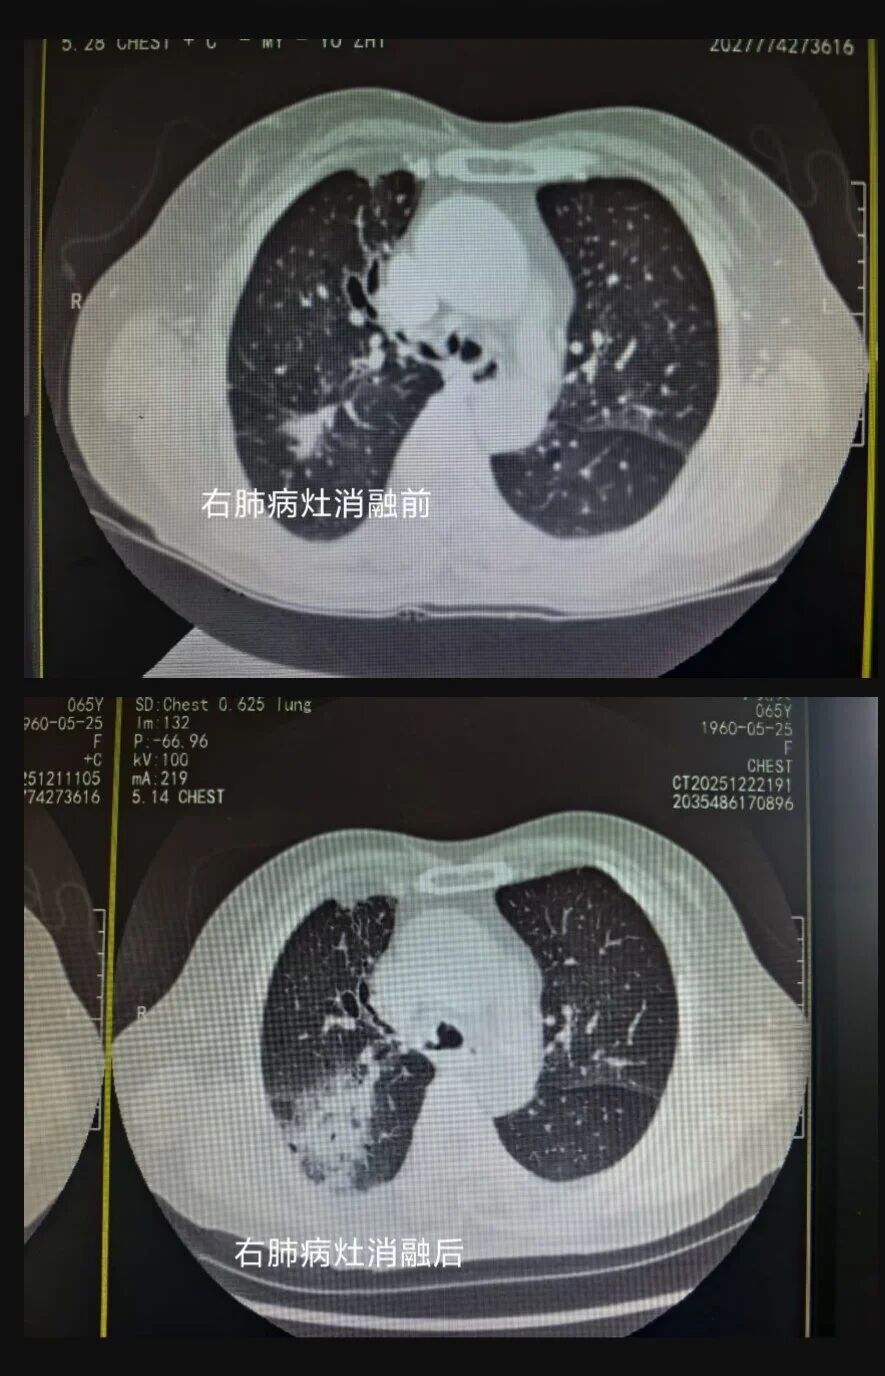

患者李某为右肺上叶结节,由于手术对患者肺功能影响较大,且患者不愿行手术治疗,经综合评估并与患者充分沟通后,胸外科团队决定为其施行CT引导下精准微波消融术。该技术能以最小创伤精准灭活病灶,最大程度保留健康肺组织。

手术由危志刚教授与县医院胸外科副主任柳长溪共同协作完成。凭借丰富的临床经验和娴熟的操作技术,团队仅用半小时便顺利完结消融。术中患者生命体征平稳,未出现出血、气胸等并发症,体表仅留微小穿刺点,真正达到了微创治疗的效果。术后在胸外科医护团队的精心治疗护理下,患者恢复顺利,2小时后即可进食并下床活动,复查胸部CT显示消融范围完全覆盖病灶,手术效果显著。